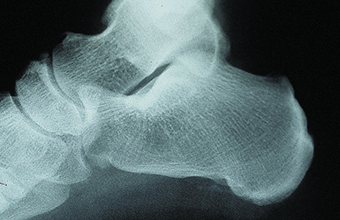

Hay estudios con resultados contradictorios sobre la fascitis plantar y su relación con los espolones del calcáneo [58][53] y está consensuado que la fasciotomía plantar aislada tiene los mismos resultados que las fasciotomías asociadas a la resección del espolón. La resección del espolón no siempre es necesaria [69]. De Prado et al., [30] recomiendan efectuar una resección sistemática del espolón pues comporta beneficios psicológicos sobre el paciente quien, habitualmente, asocia el espolón con su dolor(Figura 4) (Figura 5).

Figura 4A

Figura 4B

Figura 5A

Figura 5B

Figura 5C

Figura 4. A) espolón del calcáneo. B) al año de su resección con técnica percutánea

Figura 5. A) espolón del calcáneo. B) resección con cirugía percutánea. C) evolución al año.